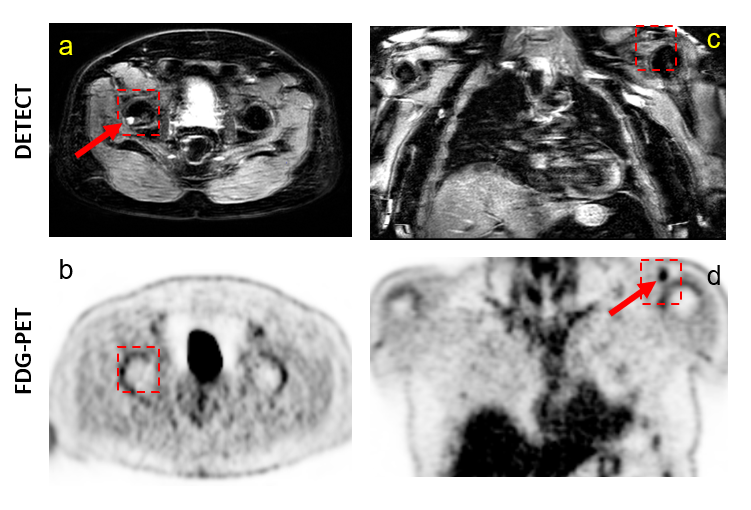

Figure 3. Representative images of WBMRI-DETECT (a, c) and FDG-PET (b, d) are shown in a 62-year-old subject where lesions appear on one modality, but not the other. (a-b) show an axial view of the pelvis where a lesion is visible DETECT (a) in the femur (red arrow), but not in the same region for FDG-PET (b). (c-d) show a coronal view of the chest where a lesion is seen in FDG-PET (d) in the AC joint (red arrow), but not in DETECT (c). However, in subjects where both FDG-PET and WBMRI have been clinically evaluated, WBMRI uniquely identified 10 lesions, and FDG-PET uniquely identified 4 lesions.